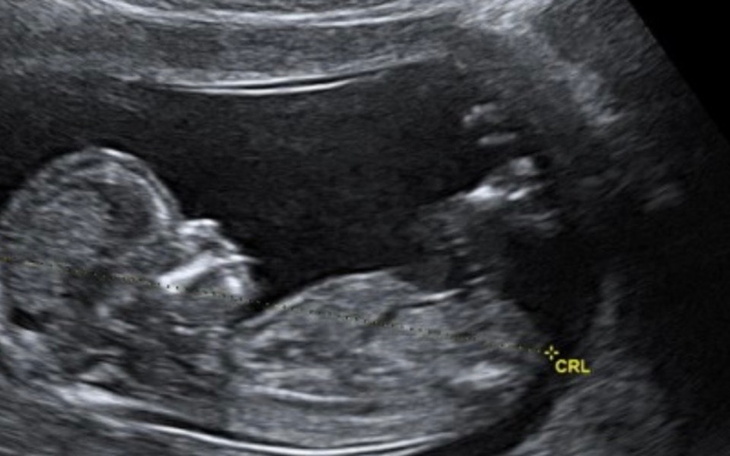

Od momentu kiedy dowiedziałam się, że jestem w ciąży, moim największym pragnieniem jest przywitanie dziecka w domu. W związku z tym zwracam się do Was z ogromną prośbą o pomoc w zorganizowaniu porodu domowego.

Zdecydowaliśmy się na tę formę narodzin, ponieważ daje nam poczucie bezpieczeństwa, komfortu i intymności, a także pozwala przeżyć ten wyjątkowy moment w zgodzie z naszymi przekonaniami.